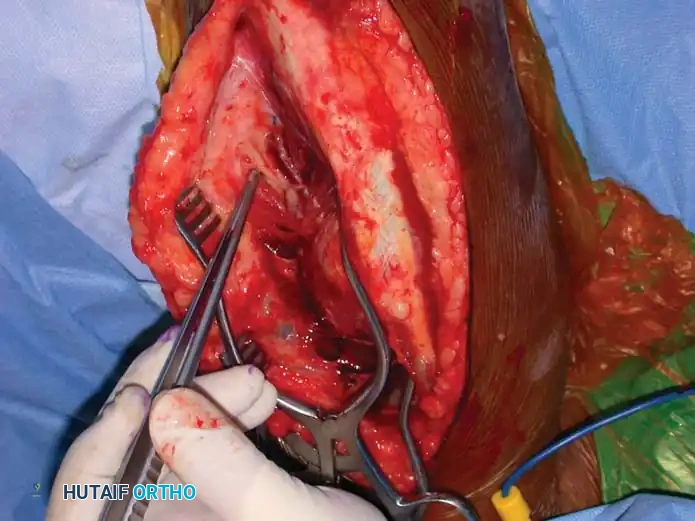

5. Deep Dissection and Radial Nerve Mobilization:

* Elevate the lateral head of the triceps off the lateral intermuscular septum.

* Identify the radial nerve and the profunda brachii artery as they pierce the lateral intermuscular septum to enter the anterior compartment.

* Carefully mobilize the radial nerve. Use vessel loops for gentle retraction. Never apply excessive traction to the nerve.

Fig. 54-33 D, Mobilization of the radial nerve.

6. Fracture Reduction and Fixation:

* Reflect the entire triceps muscle mass medially to expose the posterior humeral shaft.

* Reduce the fracture and apply the pre-selected LC-DCP. Ensure the radial nerve is completely free and not tethered beneath the plate.